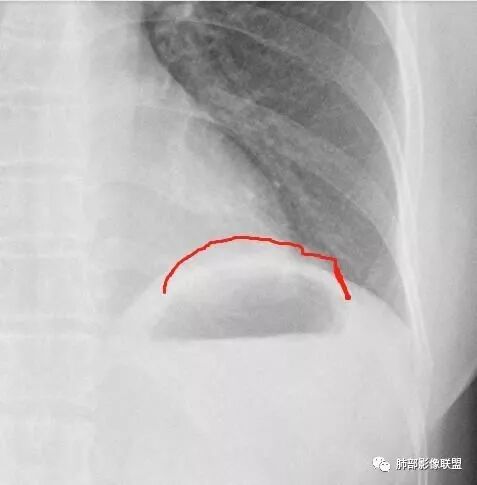

Shelia:侧位心后间隙变小,下肺野与心影重叠区怀疑有斑片影

正位实在看不出什么问题

Shelia:

南大标记的,我怀疑了,但是正位不知道在哪里远方:接第二部分:

看完第二部分大家再说说看有什么体会?宇宙星空:左侧膈面上片状高密度影

M-Imaging :盘状不张不是,盘状不张,胖人腹压高多见远方:如南大所标示,标准答案。正位提示左肺下野与膈面重叠密度增高影,边缘光滑,侧位可再定位具体一点后肋膈角区密度增高影,具体是肺内肺外都有可能,盘状肺不张、肺内肿块、肺外病变(胸膜来源和膈肌来源)等都可以。我的体会常规正片再加负片结合这个肯定不会漏的,负片很有价值,平片发现问题就好,具体我们还是进一步CT检查了。

远方:基层医院很多都是X线为主,胸片占了一半以上,专科除外,正侧位片往往不重视侧位,临床医生也经常未要求侧位,考验我们影像医生了。这个单凭正位往往就漏了。恰好病变上缘与膈肌面比较重合。